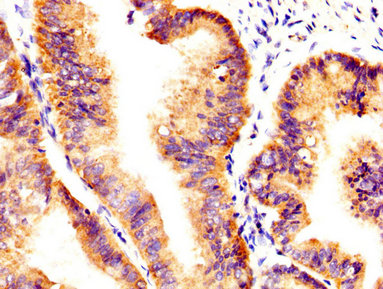

IHC image of CSB-PA326981LA01HU diluted at 1:400 and staining in paraffin-embedded human endometrial cancer performed on a Leica BondTM system. After dewaxing and hydration, antigen retrieval was mediated by high pressure in a citrate buffer (pH 6.0). Section was blocked with 10% normal goat serum 30min at RT. Then primary antibody (1% BSA) was incubated at 4°C overnight. The primary is detected by a biotinylated secondary antibody and visualized using an HRP conjugated SP system.